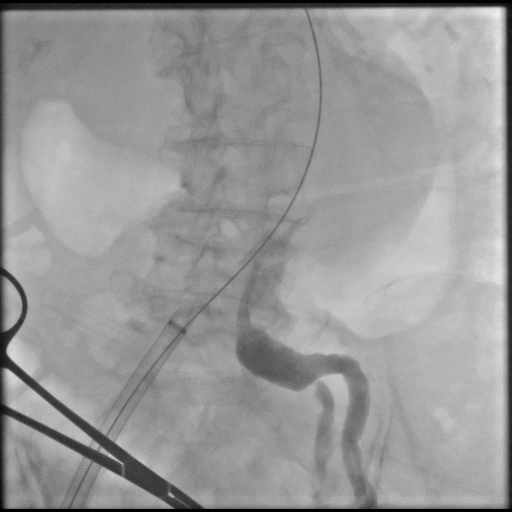

Under general anesthesia, bilateral common femoral arteries were accessed percutaneously under ultrasound guidance, and the pre-close technique with Perclose ProGlide (Abbott Vascular, USA) was applied. Angiography confirmed a large infrarenal AAA and left common iliac artery with severe stenosis (>70%) and marked tortuosity, while the right iliac was relatively straight. Guidewire advancement through the left side was difficult due to narrowing and vessel curvature.

Percutaneous transluminal angioplasty (POBA) was performed on the proximal left common iliac artery using a 10 ¡¿ 80 mm Mustang balloon (Boston Scientific, USA) inflated and showing a balloon-waist formation consistent with a tight, fibrotic lesion. After gradual dilation up to 6 atm, the waist resolved and the lumen expanded, allowing smooth wire and sheath passage. The SEAL NOVUS stent-graft system (S&G Biotech, Korea) was used, with the main body (24 ¡¿ 50 mm) introduced via the right common femoral artery. Two flared iliac limbs, 12(18) ¡¿ 100 mm on the left and 12(16) ¡¿ 80 mm on the right, were deployed in a ballerina (crossed-limb) configuration to accommodate left-sided tortuosity and prevent kinking. During contralateral limb cannulation, angiography was performed within the main body to confirm the wire course inside the graft before advancing the sheath. Completion angiography demonstrated a Type Ia endoleak, treated with proximal neck flaring using a Coda LP balloon (Cook Medical, USA) under a rapid inflation–deflation technique to optimize sealing and prevent graft migration. Final angiography showed excellent proximal seal and bilateral flow, and follow-up CTA confirmed durable aneurysm exclusion without endoleak.